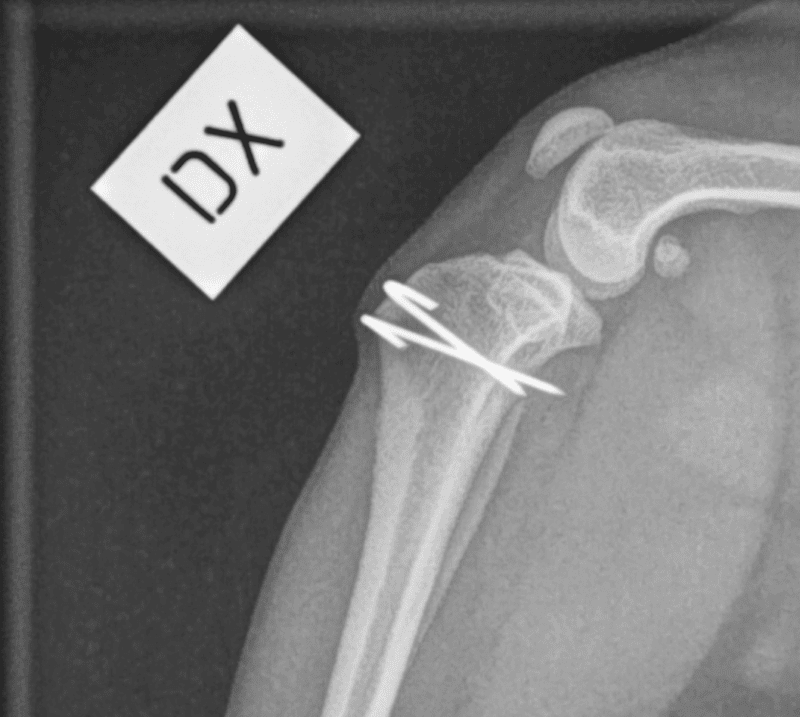

Diagnoosi tehdään yleensä fyysisen tutkimuksen avulla, jossa eläinlääkäri arvioi polven liikkuvuutta ja vakautta. Röntgenkuvat voivat olla tarpeen muiden mahdollisten ongelmien poissulkemiseksi ja polven rakenteen tarkemmaksi arvioimiseksi. Pyynikin eläinlääkärit tarjoavat kattavat diagnostiikkapalvelut, jotka auttavat selvittämään polvilumpion sijoiltaanmenon laajuuden ja mahdolliset hoitovaihtoehdot.

Vakavammissa tapauksissa leikkaus saattaa olla tarpeen polven rakenteen korjaamiseksi ja polvilumpion vakauttamiseksi. Leikkausmenetelmiä on useita, ja eläinlääkäri valitsee sopivimman menetelmän koiran yksilöllisten tarpeiden mukaan.